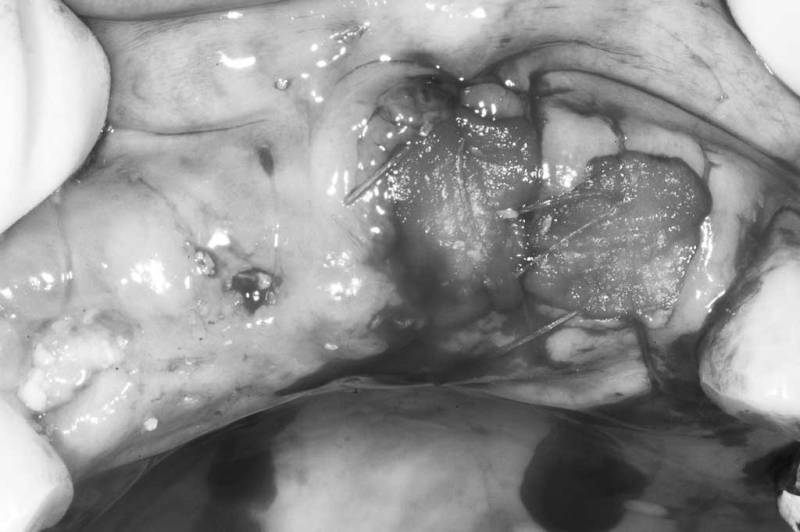

窩洞保存術術中